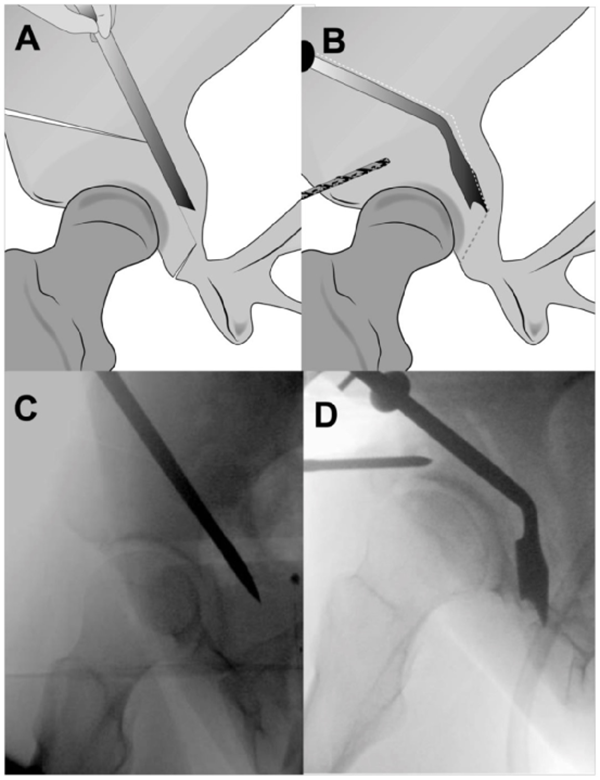

A.图显示用倾斜的Ganz骨刀进行髋臼下截骨。B.后柱的侧视图,显示向坐骨棘倾斜的不完整坐骨截骨。需要多次内侧和外侧击打确认截断整个厚度的坐骨。在截骨过程中伸展下肢,保护坐骨神经